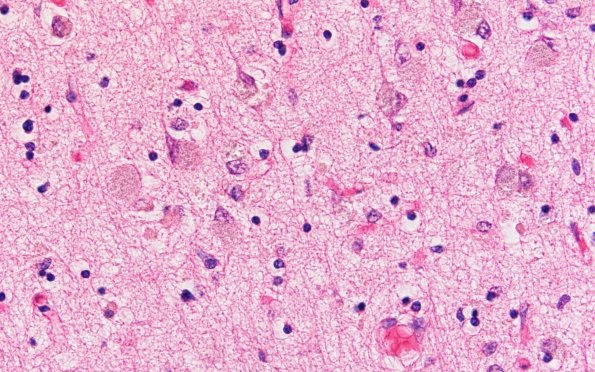

Washington University Experience | METABOLIC | Neuronal Ceroid Lipofuscinosis (NCL) | 7B4 NCL (Case 7) Occip H&E 60X

The microscopic appearance of the occipital cortex confirms neuron loss, astrocytosis and residual neurons with stored material. (H&E)